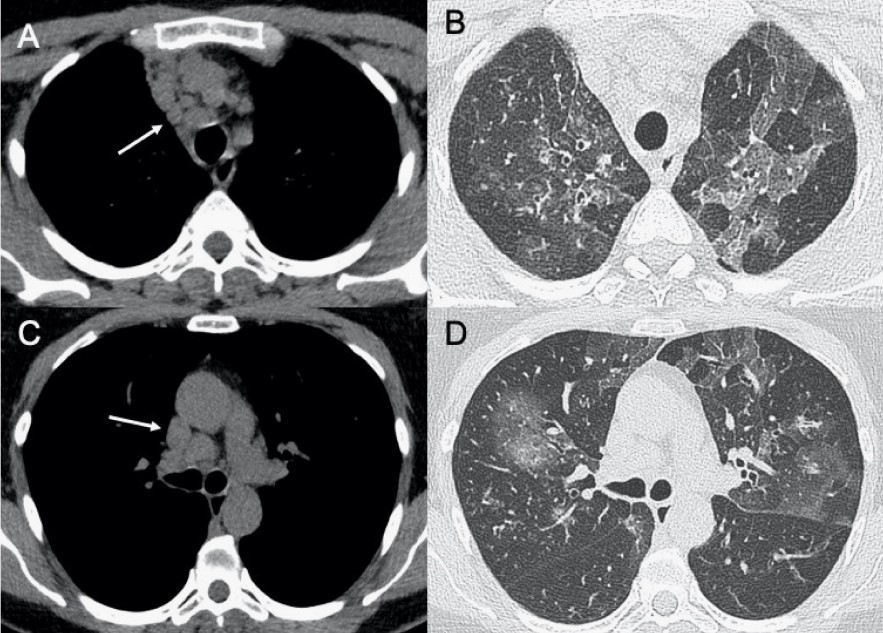

?EB病毒

● CXR:淋巴結(jié)腫大,雙肺間質(zhì)實(shí)質(zhì)受累。

● CT:淋巴結(jié)腫大和較少見的間質(zhì)浸潤伴彌漫性GGO和實(shí)變。

圖9 EB病毒性肺炎。圖(A,C)顯示縱隔淋巴結(jié)腫大(箭頭),與雙肺局灶性小葉GGO相關(guān)(B,D)。